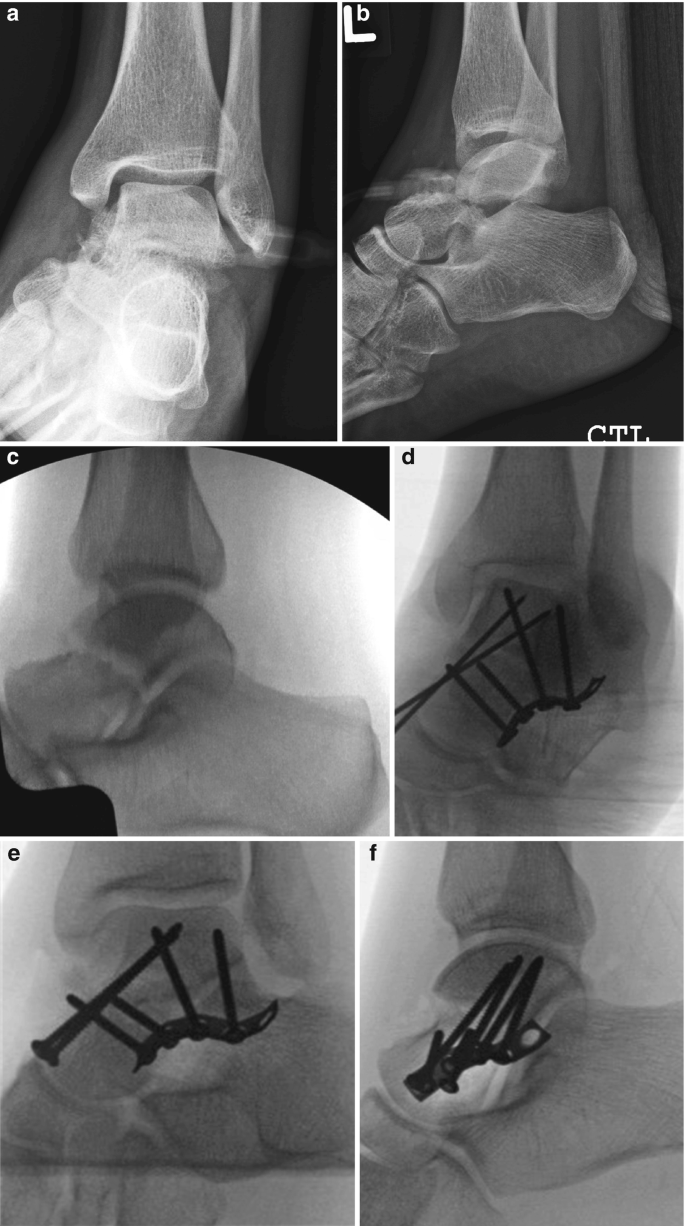

talus fracture

» Talus fracture approach (95) 사진

Talus fracture approach (95) 사진